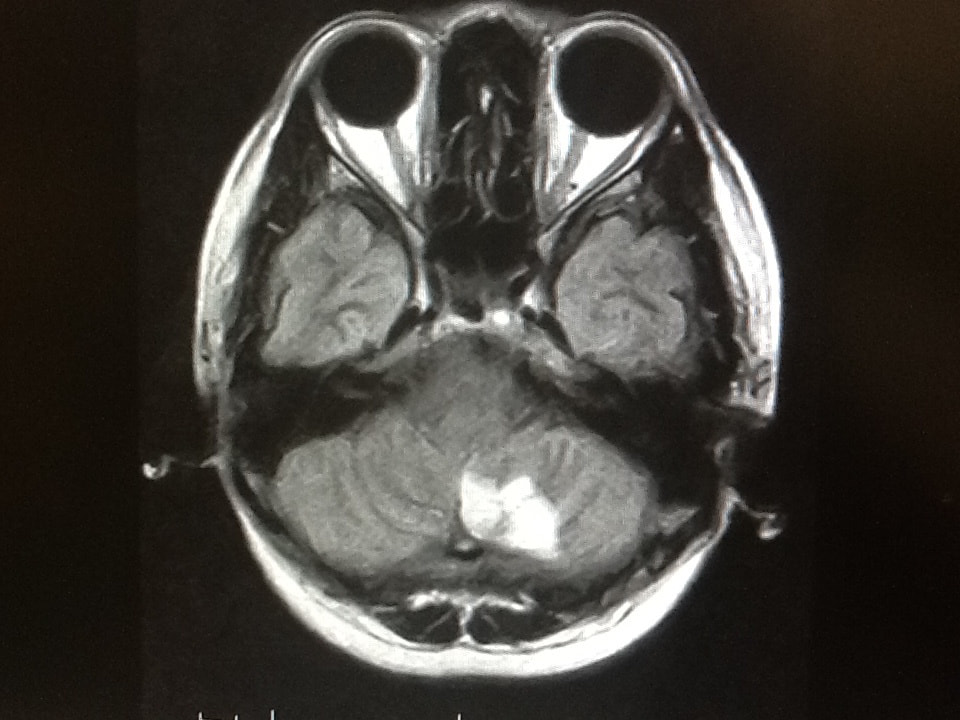

1|脳MRIドック

自覚症状がない方にも脳梗塞が生じている場合があります。この検査は痛みを伴わずに脳梗塞の有無と大きさ、場所、そしてまれに発見される脳腫瘍の有無や脳の萎縮などをチェックする検査です。

所要時間:30分  費用:22000円(消費税込み)